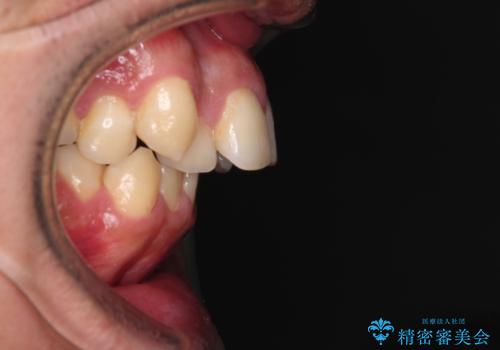

舌の突出癖などにより上顎前歯が前方に突出し、さらに歯列幅が狭小になっている状態でした。

また、上顎歯列全体が下顎に対して前方位に位置していました。

上顎歯列幅を側方に拡大するとともに、歯列全体を後方に移動させるためのアンカースクリューと補助装置を使用し、上顎左右第一小臼歯2本、下顎左右第二小臼歯2本、計4本を抜歯し、ワイヤー装置にて矯正治療を行うこととしました。